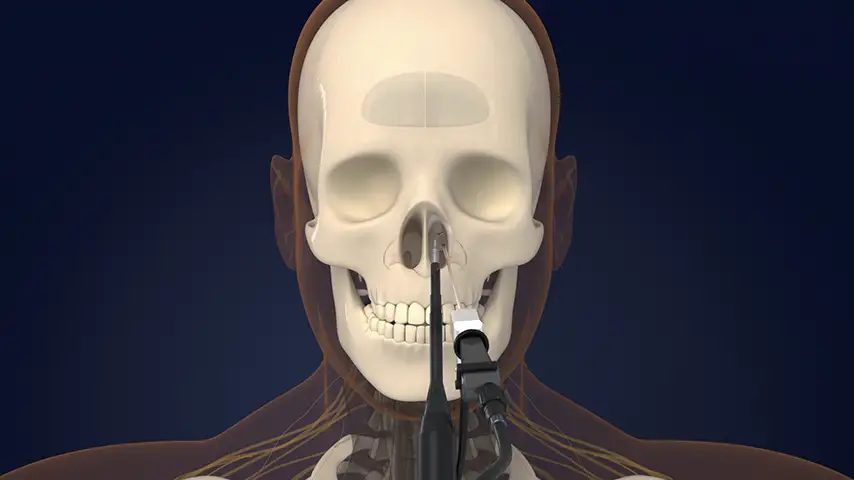

in Endoscopic and Microscopic Surgery

Posterior sphenoidotomy for pituitary tumor removal

DCR (Dacryocystorhinostomy)